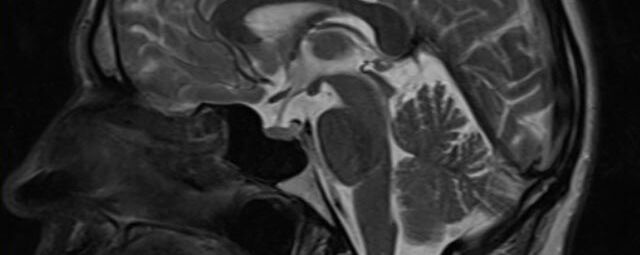

- Diffusionswichtung

- Perfusionswichtung

- Suszeptibilitätswichtung

- MR-Spektroskopie

Diese Verfahren werden bei verschiedenen Fragestellungen in verschiedenen Körperregionen in die Messprotokolle sinnvoll eingefügt. Teilweise können dadurch Differenzierungenverschiedener krankhafter Prozesse verbessert werden.